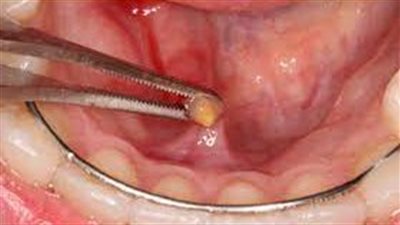

كل ما تريد معرفته حول حصوة اللعاب (الأسباب)

تعرف على أعراض وأسباب الحصوة اللعابية